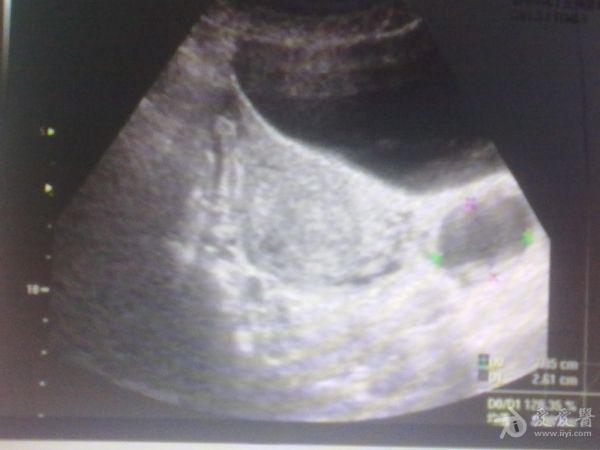

左侧卵巢囊肿?

39岁女性继发性

不孕

,月经第12天

超声

检查:左侧附件区见大小约3.6x2.7cm类圆形无回声,边界清,内透声好,右侧卵巢建多个大小不等极不规则囊泡回声,最大约1.2x1.4cm。这几幅图探头标记都在患者的右侧,也就是标记冲向我。,,显示器上的M标记在显示器的左上方。囊肿是在左侧卵巢吗?